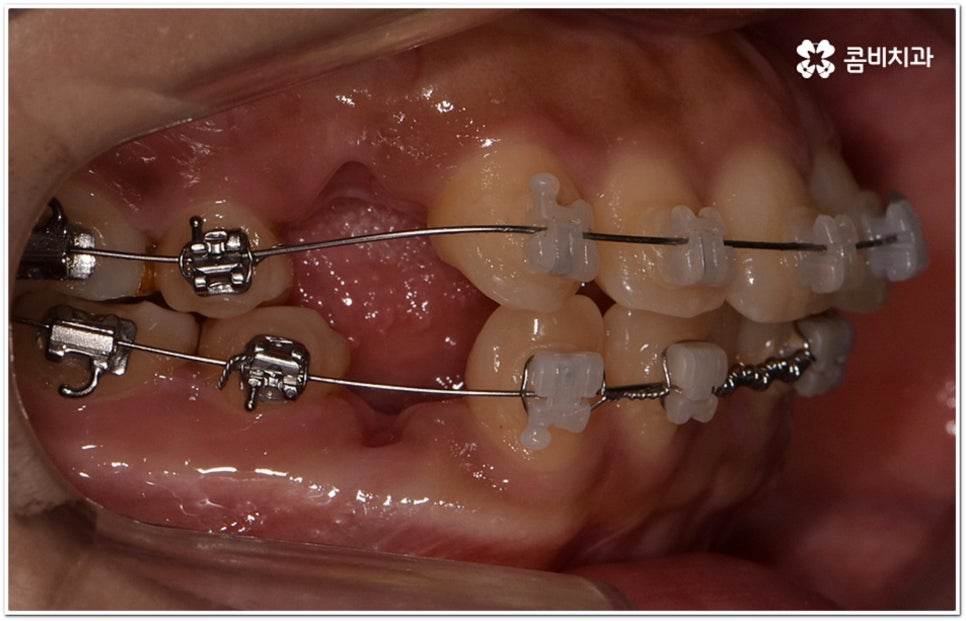

환자마다 치열, 교합, 치아가 튀어나온 각도, 잇몸이 드러나는 정도, 상악과 하악의 구조 및 관계 등 턱관절 관련 부분 상황이 모두 다르기 때문에 3D CT 같은 정밀 검진 기계를 통해 이를 꼼꼼하게 살펴보고 각각에 맞는 계획을 세밀하게 세워 교정 치료를 진행해 줄 필요가 있어요. 이때 환자분들의 상황에 따라 양악수술과 같은 외과적인 방법을 병행해야 하는 케이스도 있을 수 있기 때문에 돌출입을 가지고 계신 분들 중에서 수술에 부담을 느끼고 지레 치료를 포기하신 분들도 있을 수 있는데 정도가 많이 심각하지 않고 구조적인 원인이 크지 않다면 대부분의 케이스는 치아교정 만으로도 충분히 개선이 가능하니 먼저 돌출입교정치과 에 들러서 정밀 검사를 진행한 후 치료 방향에 대해 의료진과 논의해 보시면 좋을 거예요.

말씀드렸던 것처럼 돌출입의 원인이 치아 만의 문제, 즉 각도가 살짝 앞으로 뻐드러진 데 있고 상태가 그다지 심한 것 같지 않다면 보다 빠르고 간편한 수복이 가능할 수 있어요. 튀어나온 부분을 집어넣기 위해서는 발치가 필수적이지 않을까 생각하실 수 있는데 후방으로 이동시켜 줄 공간이 충분하다면 치간 삭제, 악궁 확장, 어금니 후방 이동 등 다른 방법을 이용하여 비발치 치료 과정을 진행할 수 있으므로 너무 걱정하지 않으셔도 될 거예요. 오히려 환자분들의 다양한 상황을 고려하지 않고 무리하게 발치 교정을 진행하게 되면 옥니나 합죽이와 같은 부작용이 일어날 수도 있기 때문에 원인을 정확하게 파악하고 적절한 치료를 할 수 있도록 임상 경험이 풍부하고 뛰어난 노하우를 가지고 있는 숙련된 의료진에게 교정 치료를 맡기시는 것이 굉장히 중요하다고 할 수 있습니다.

또한 구조적인 부분에 원인이 있었다면 교정 치료를 받은 후에도 원래대로 치열이 돌아가려고 하는 회귀 경향이 좀 더 강하게 일어날 수 있어요. 그렇기 때문에 치과에서 말씀드린 유지 장치를 잘 착용하면서 사후 관리를 철저하게 해 줘야 보다 오랜 시간 동안 바른 치열을 유지하면서 이를 건강하게 사용할 수 있습니다.

가철식(뺐다 꼈다 할 수 있는) 유지 장치는 눈에 잘 띄지 않고 식사를 할 때나 중요한 자리에서 잠깐씩 뺄 수 있다는 장점을 가지고 있지만 착용하는 시간이 부족하게 되면 혹여 치열이 다시 삐뚤어지거나 교합이 어긋나게 되어 심한 경우 재교정을 받아야 하는 상황까지도 이를 수 있기 때문에 교정이 끝난 초기에는 환자분들께서 주의를 기울여서 불가피한 경우가 아니라면 계속해서 착용을 해주시길 권고드리고 있어요. 그 이후에는 치료하신 치과의 안내에 따라 착용 시간을 줄여가면서 정기적인 검진을 받으시면서 관리를 해주시는 게 좋아요. 이에 반해 고정식 유지 장치는 착용 시간을 신경쓰지 않아도 되지만 부착시킨 철사로 인해 칫솔질이 어려워지고 치석이 잘 생기는 등 위생 문제가 발생할 수 있다는 점을 유의해야 하므로 주기적으로 검진을 받으면서 스케일링 치료를 통해 구강 내 위생 관리를 철저하게 해 주면 도움이 될 거예요. 가장 좋은 것은 고정식 유지장치와 가철식 유지장치를 둘 다 착용을 하시는 게 도움이 되므로, 치료를 담당하시는 원장님과 자세히 상담받아보시길 권장 드려요.